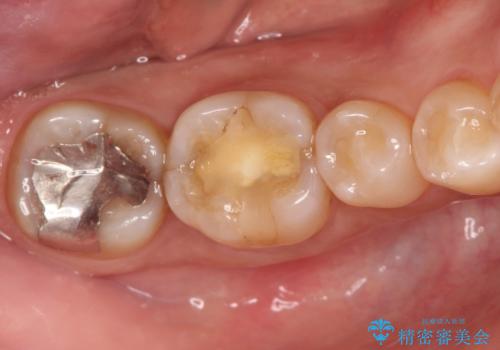

- 1週間前から冷たいもので強い持続痛を感じることを主訴に来院されました。

歯髄診断と痛みの再現により原因歯を特定し、症候性不可逆性歯髄炎の診断となりました。

根管治療〜オールセラミッククラウン(エクセレント)の治療を行なっております。